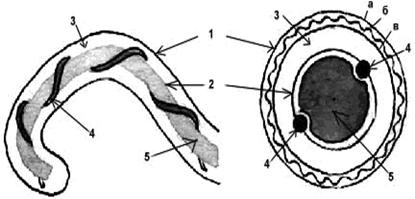

Структура клетки лептоспир.

Обозначения: 1-наружная мембрана; 2-периплазматический цилиндр; 3-жгутик: - 1-наружная мембрана (а, б, в-ее слои); - 2-внутренняя мембрана; 3-периплазматическое пространство; 4-жгутики; 5-цитозоль

Структура клеточной стенки лептоспиры аналогична таковой других спирохет. 3–5-слойная наружная мембрана окружает протоплазматический цилиндр, покрытый гибким пептидогликановым слоем, тесно ассоциирванным с внутренней цитоплазматической мембраной, как у грамположительных бактерий. В этих слоях отсутствуют гликолипиды. В пептидогликане преобладает орнитин, а не диаминопимелиновая кислота, как считалось ранее.

Наружная мембрана лептоспиры весьма необычна, поскольку является самой жидкой из известных на сегодняшний день. Находящиеся в ней наружные мембранные протеины при движении всегда (даже при изменении направления) смещаются в задний конец клетки. Скорость дрейфа антигенов в мембранах приблизительно составляет 11 мкм/сек.

Оболочка клетки окружает так называемый «протоплазматический цилиндр». Благодаря укорочению закрученных вокруг него осевых нитей последний имеет винтообразную форму.

Два жгутика (осевые нити) диаметром 20–30 нм локализуются в периплазматическом пространстве между наружной мембраной и пептидогликановым слоем оболочки. Их свободный конец уже внутриклеточного. Аксиальная нить состоит из сердцевины диаметром 11,3 мкм, окруженной 2 мембранными слоями толщиной 21,5 и 42 микрон. Она прикрепляется крючком к базальному тельцу на противоположном конце периплазматического цилиндра и идет вдоль оси клетки приблизительно до ее центра. Аксиальные нити не перекрываются между собой, как это имеет место у других спирохет. Структура базальных телец жгутиков такая же, как и у других грамотрицательных бактерий. Аксиальные нити обеспечивают движение и сохранение лептоспир своей формы. В культурах лептоспиры нередко образуют клубки, а по мере старения в них появляются дегенирирующие формы с атипичной морфологией.